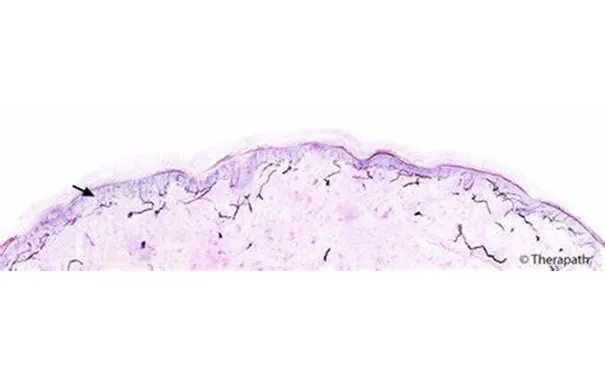

8、皮肤和神经活检:皮肤活检取胫前皮肤3mm,测量表皮内神经纤维(IENF)密度和分支长度,有助于诊断小纤维神经病;神经活检取踝后方腓肠神经,主要用于和其他疾病的鉴别。